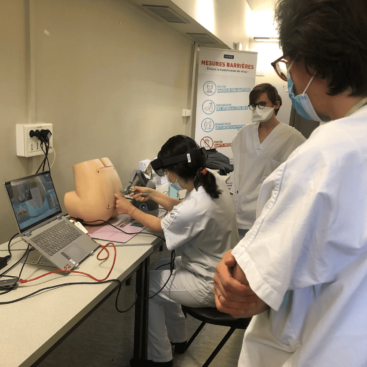

“Sim&Care really allows sensations very close to reality and it’s a nice meeting we had with the startup InSimo who had developed this expertise in force feedback.

“We developed a collaboration in a few months and my service was in charge to test technical advances and the realistic side of the device. We also ask our students to check the applicability of this device and its pedagogical value. InSimo regularly visits the department with its devices and we have built a great collaboration[…]”